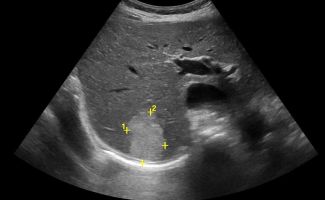

Το Yπερηχογράφημα Kάτω Kοιλίας αξιολογεί την ουροδόχο κύστη και τα έσω γεννητικά όργανα. Η πλήρωση της ουροδόχου κύστεως είναι απαραίτητη για τη διερεύνηση παθολογιών όπως:

- Λιθίαση

- Τοιχωματικές βλάβες

- Συμπαγείς βλάβες (όπως θηλώματα)

Στους άνδρες, αξιολογείται ο προστάτης, με μέτρηση των διαστάσεων και εκτίμηση του βαθμού υπερτροφίας και του κυστικού υπολείμματος μετά την ούρηση.

Στις γυναίκες, εξετάζονται η μήτρα και οι ωοθήκες, με μέτρηση του πάχους του ενδομητρίου και διερεύνηση για βλάβες όπως:

- Ινομυώματα

- Πολύποδες

Οι ωοθήκες ελέγχονται για την αξιολόγηση της μορφολογίας τους και πιθανών κύστεων ή συμπαγών βλαβών, καθώς και για τον έλεγχο σε περιπτώσεις υποψίας συνδρόμου πολυκυστικών ωοθηκών.